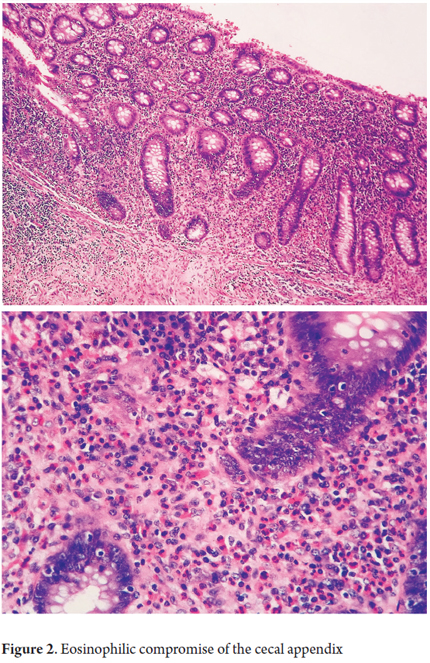

Microscopic examination will find dense, predominantly eosinophilic, inflammatory infiltrate in which there can be up to 20 eosinophils per high-power field (Figure 1). This infiltrate is distributed in the lamina propria and may also be accompanied by formation of aggregates in crypt abscesses that permeate the glandular epithelium. These can be distributed in diffuse or nodular patterns and can be accompanied by outbreaks of ulceration of the glandular epithelium with regenerative alterations and severe edema. Tissue damage may extend beyond the mucosa into the muscle and serous layers (Figure 2). In addition, up to 10% the study of mucosal biopsies may show no changes (Figures 3 and 4). At least six biopsies may be required to reach a diagnosis of one segment (15-17).